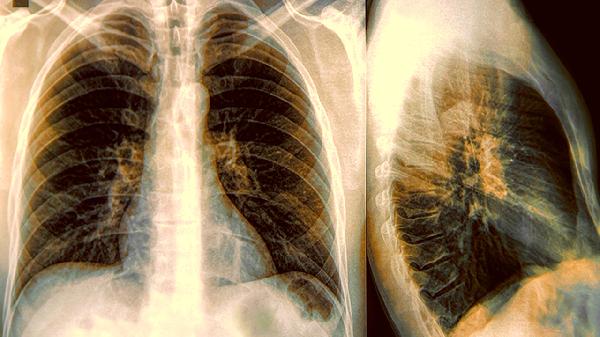

胸膜炎可能與肺部感染、結核桿菌感染等因素有關(guān),通常表現為深呼吸時(shí)加重的尖銳胸痛,可伴隨咳嗽、發(fā)熱??稍卺t生指導下使用頭孢呋辛酯片、利福平膠囊、對乙酰氨基酚片等藥物抗感染治療。建議臥床休息,采取患側臥位減輕疼痛。

氣胸可能與肺大皰破裂、胸部外傷等因素有關(guān),通常表現為突發(fā)性刀割樣胸痛伴呼吸困難。輕度氣胸可通過(guò)吸氧觀(guān)察,中重度需進(jìn)行胸腔閉式引流術(shù)或胸腔鏡手術(shù)。術(shù)后避免劇烈咳嗽,定期復查胸片。